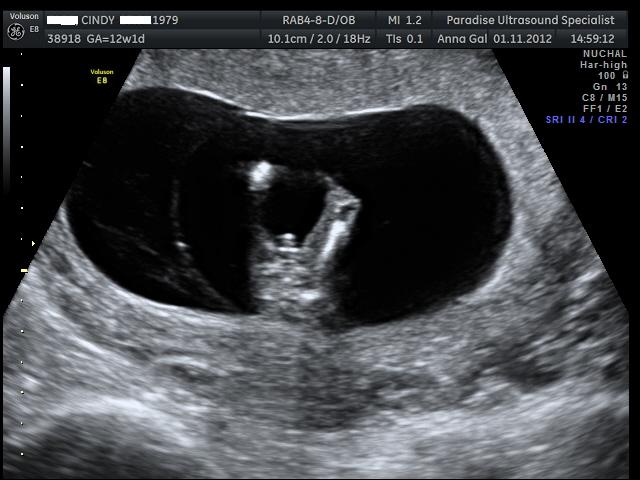

Here are the pics from my NT scan, the tech had a guess she said she is 70% positive the sex is.... can you guess? UPDATE - It's a boy :)

Attachment 5832 Cinss!!!!!

Do I have to say anything else? ;)

100% :diaper: